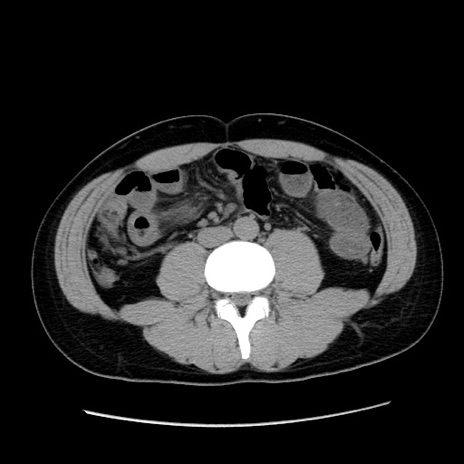

症例36(横断像)

【症例】20歳代 男性

【主訴】心窩部痛

【現病歴】今朝より上腹部痛あり。一旦軽快していたが再度出現したため救急要請。昨日夕に白身の魚を含む刺身を食べた。

【身体所見】BP 136/89mmHg、HR 74/min、BT 37.0℃、腹部:膨満、軟、心窩部に圧痛あり。反跳痛なし、筋性防御なし、腸雑音やや亢進あり。

【データ】WBC 17700、CRP 0.48